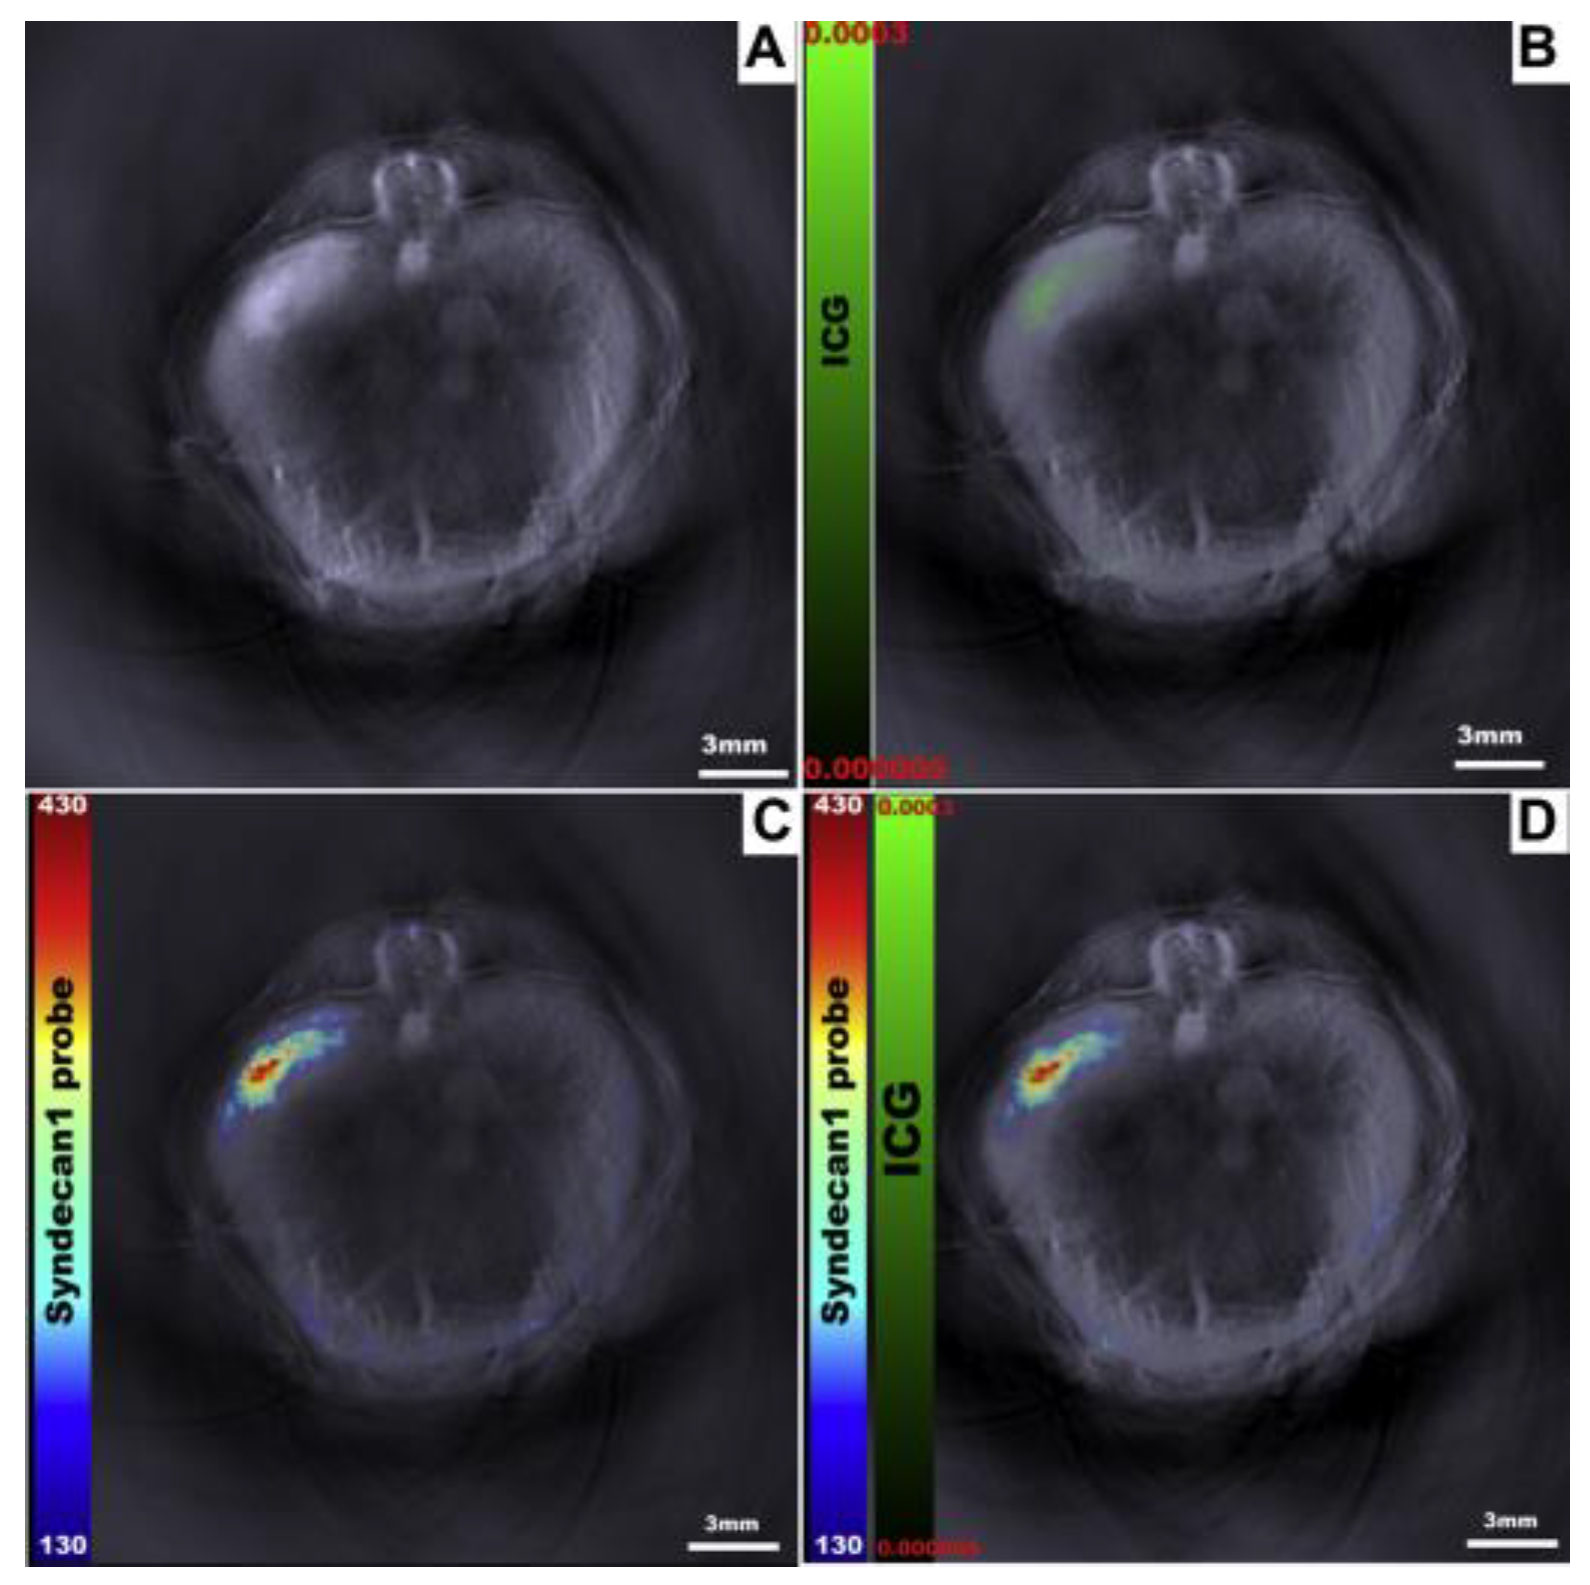

- Kimbrough, C.W.; Hudson, S.; Khanal, A.; Egger, M.E.; McNally, L.R. Orthotopic pancreatic tumors detected by optoacoustic tomography using Syndecan-1. J. Surg. Res. 2015, 193, 246–254. [Google Scholar] [CrossRef] [PubMed]

- Napp, J.; Stammes, M.A.; Claussen, J.; Prevoo, H.; Sier, C.F.M.; Hoeben, F.J.M.; Robillard, M.S.; Vahrmeijer, A.L.; Devling, T.; Chan, A.B.; et al. Fluorescence- and multispectral optoacoustic imaging for an optimized detection of deeply located tumors in an orthotopic mouse model of pancreatic carcinoma. Int. J. Cancer 2018, 142, 2118–2129. [Google Scholar] [CrossRef] [PubMed]